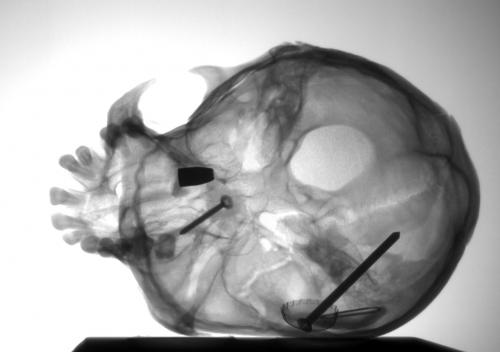

You’ve got a screw loose – Xray of Skull with Screws in.